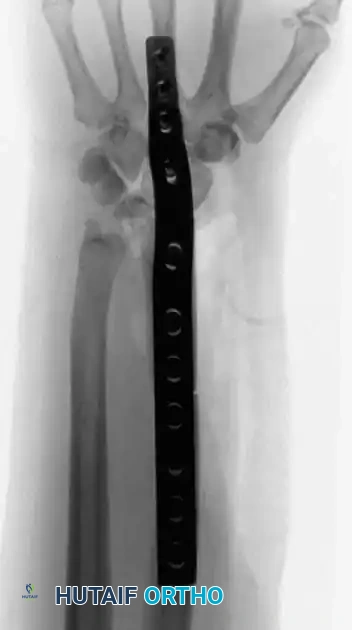

In cases involving the distal radius (a common site for aggressive epiphyseal tumors like GCT), en bloc resection of the distal radius is performed. The tumor is excised with wide margins, sacrificing the radiocarpal joint.

To reconstruct the defect and restore forearm length, a structural autograft is harvested. The contralateral proximal fibula is an excellent anatomical match for the distal radius.

The fibular autograft is contoured and impacted into the medullary canal of the remaining radial diaphysis. A rigid wrist fusion plate is then applied dorsally, spanning from the radial shaft, across the fibular graft, and securing to the carpal bones (typically the capitate and third metacarpal) to achieve a stable radiocarpal arthrodesis.